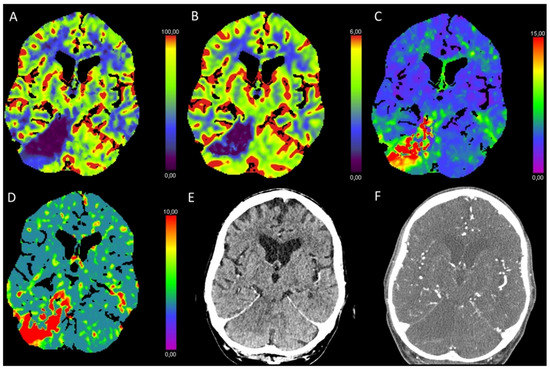

3.3. Global Hypoxic-Ischemic Injury/Brain Death

| Brain death | ↓↓ | ↓↓ | ↑↑ | ↑↑ |